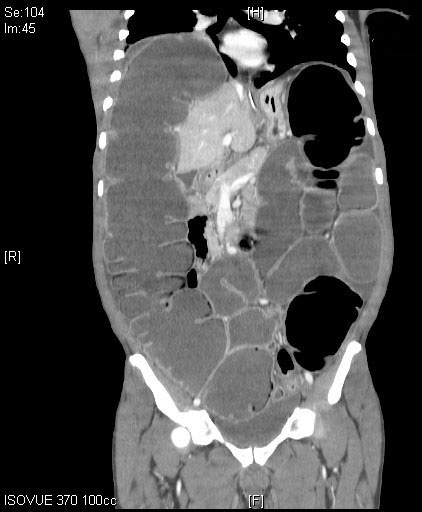

Computed tomography (CT) imaging of the abdomen and pelvis is a far more sensitive and specific tool in the assessment of LBO. (See Figures 1 and 2.) CT imaging offers significantly more information than an abdominal X-ray, including the location of the occlusion, the possible etiology of the LBO, and/or any complications from the LBO, such as perforation.1,5 CTs can localize obstructing lesions with a reported sensitivity of 96% and specificity of 97%, making them highly effective at identifying the transition point from healthy to affected bowel.2,6

Figure 1. Coronal Plane of a Computed Tomography Scan of the Abdomen and Pelvis Demonstrating a Dilated Large Bowel, Consistent with Large Bowel Obstruction |

Source: Image courtesy of J. Stephan Stapczynski, MD. |